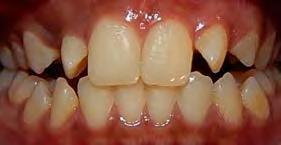

Se presenta una paciente de 17 años y 5 meses diagnosticada con clase I esquelética, hipodivergente, clase I molar y canina izquierda, clase II molar derecha y la clase canina derecha sin identificar debido al canino 13 retenido, mordida abierta en sector de laterales, overjet y overbite disminuidos, línea media dental superior desviada a la derecha y la inferior desviada a la izquierda, microdoncia de los incisivos 12 y 22. Objetivo: mantener el perfil facial, y las relaciones esqueléticas maxilomandibulares, realizar cirugía del 13, corrección de rotaciones dentales en el maxilar, mantener la clase I molar izquierda y obtener la clase I molar derecha, mantener la clase I canina izquierda, obtener clase I canina derecha, cerrar mordida abierta de sector de laterales, corrección del overjet y overbite, corrección de líneas medias dentales, manejo de Bolton, mejorar estado periodontal, lograr correcta intercuspidación, guía de desoclusión canina e incisiva y restauración de los dientes 12 y 22. Tratamiento: alineación, nivelación, tracción canina del 13, detallado y retención. Tiempo de tratamiento: 2 años y 9 meses.

Caso clínico

Se presenta una paciente de 13 años 5 meses con el motivo de consulta “es que no me baja el colmillo”. En los estudios extraorales se ve el perfil concavo y labios en contacto durante el reposo (Figura 1). En los estudios intraorales tenemos , clase I esquelética, con crecimiento hipodivergente (Figura 2), clase II molar derecha y clase I molar y canina izquierda, la clase canina derecha no determinada

Figura 1. Perfil, frente en reposo, sonrisa.

(ND), órgano dental (OD) 13 retenido, mordida abierta en sectores laterales, overjet de 3 mm y overbite de 10%, líneas medias dentales desviadas y microdoncia de OD 12 y 22.

Resultados

El tiempo de tratamiento fue de 2 años y 9 meses se lograron los objetivos del tratamiento manteniendo el perfil facial, y las relaciones esqueléticas maxilomandibulares. Se realizó la tracción del 13, la corrección de rotaciones dentales en el maxilar, se mantuvo la clase I molar izquierda y se obtuvo la clase I molar derecha. La clase I canina izquierda, y se logró la clase I canina derecha, cerrar mordida abierta de sectores laterales, corrección del overjet y overbite, corrección de líneas medias dentales, manejo de Bolton de arcada superior, mejorar estado periodontal, lograr correcta intercuspidación, guía de desoclusión canina y guía incisiva y la restauración de los dientes 12 y 22

Estudios intraorales finales en las fotografías oclusales, se ven los laterales 12 y 22, así como la incorporación del canino al arco con torque adecuado (Figura 6). En la lateral derecha e izquierda la restauración estética de los laterales superiores,

sin rotaciones ni discrepancia de Bolton.